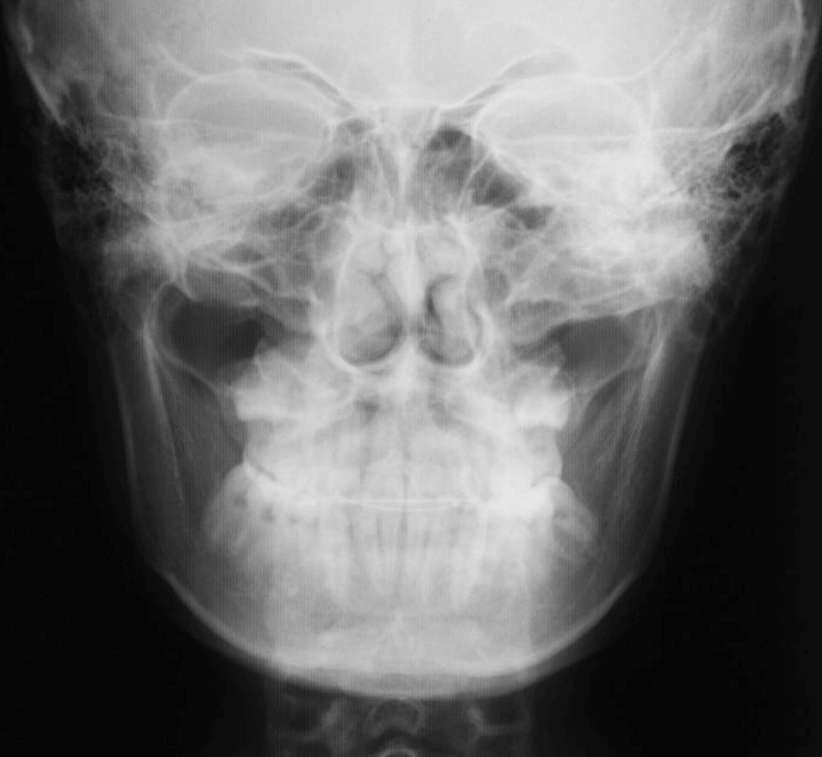

STEP2 精密検査

カウンセリング後、本格的に治療を進めるために精密検査に移ります。より詳しい口腔内の検査、顔・口内の写真撮影、レントゲンやCT撮影、歯型取りが具体的な内容です。顎の骨の歪みをはじめ、骨格的な問題が無いかも診察します。

診断結果 | 8歳3か月の男児。 左上1番(中切歯)と左上2番(側切歯)が埋伏し、発育方向にも異常が認められました。加えて、一部先天性欠如も確認されており、歯列全体の成長に影響を及ぼす可能性があると診断されました。 |